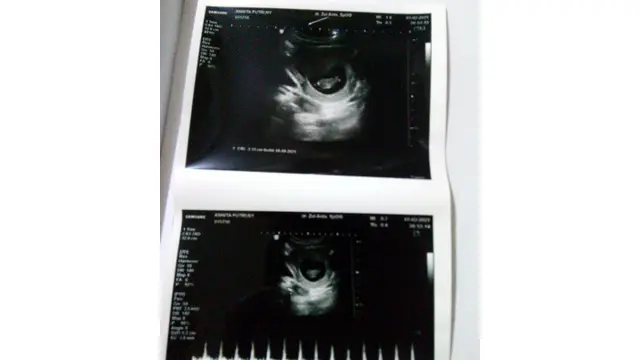

Berbeda dengan Ramadan sebelumnya, kali ini aku merasakan sedih sekaligus bahagia. Dulu selalu sibuk dengan pertanyaan kapan menikah dan tahun ini keinginan tersebut akhirnya telah terpenuhi. Tuhan telah mengabulkan permintaan orangtuaku. Anak perempuan pertama mereka kini telah menikah dan juga telah hamil saat sekarang ini. Sungguh suatu rahmat dan kenikmatan yang tiada tara.

Dengan kehadiran bayi mungil di rahimku aku mulai merasa tenang. Banyak cerita yang aku dengar dari orang yang sudah menikah bertahun-tahun lamanya belum juga dikaruniai anak. Sementara aku langsung diberikan amanah oleh Allah SWT merasakan kehamilan. Walau agak berat rasanya saat ini dengan kehamilan muda yang aku rasakan. Seringkali aku merasa mual dan pusing. Inilah juga penyebab aku harus menghentikan keinginanku untuk berpuasa tahun ini.

Padahal aku sudah merasakan senang dengan adanya kelonggaran dari pemerintah mengadakan salat tarawih di masjid tahun ini. Tapi tetap saja aku tidak bisa menikmatinya karena aku harus menjaga kandunganku saat ini. Aku takut terjadi suatu hal yang tidak diinginkan jika memaksakan diri puasa dan pergi salat Tarawih ke masjid. Orangtuaku dan juga mertuaku selalu mengingatkan agar aku selalu menjaga kesehatan dan menjaga kehamilanku saat ini. Dan aku tidak ingin membuat mereka kecewa.